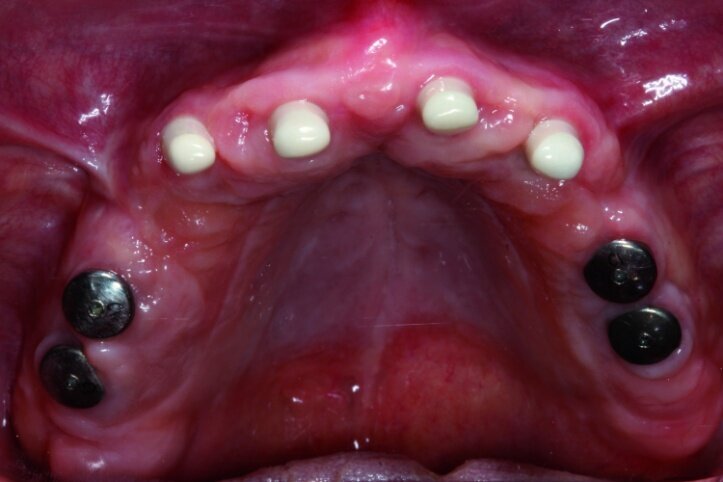

In the next phase, implants were inserted. In compliance with the results of the CBCT study, a sinus lift procedure was performed with a simultaneous implantation in the region of lateral teeth. Eight Ankylos implants were introduced, raising both maxillary sinuses at the same time. After six weeks, the implant exposure procedure was performed. Because of the fact that implants were partially anchored into the bone at the lateral section, partially within the augmentation material while primary stability was achieved, we decided to expose implants at lateral sections without occlusal load so as to perform the so-called bone training with a view to improving the condition of the bone being regenerated. An impression was taken (Figs. 7 & 8) for the positional model and for the preparation of the temporary prosthesis based on telescopes.

The model was scanned while the abutments were made ready in such a way that they could serve as telescopic crowns, also in the final stage (Fig. 9). Primary and secondary telescopic crowns were designed on the abutments (Figs. 10 & 11) on the assumption that secondary crowns had been made ready twice, that is, for the sake of temporary prosthesis and at the same time for gluing it into the final construction (Figs. 12 & 13). Abutments were mounted on implants by means of Pattern Resin (Figs. 14 & 15) in such a way that the position does not change during mounting.